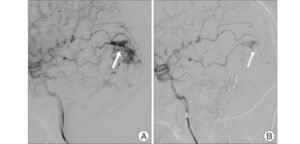

- Surgical Treatments: If medications are not effective, surgical options might be considered. Procedures like microvascular decompression can relieve pressure on the trigeminal nerve, while other techniques may involve destroying the nerve or disrupting pain pathways.